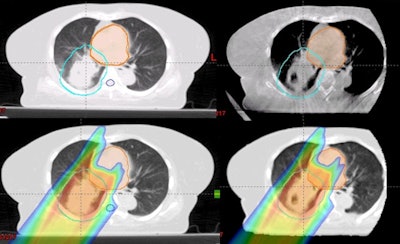

In their new study, Boon-Keng Teo, PhD, a radiation oncologist at the University of Pennsylvania, and colleagues, has developed a CBCT-based workflow for adaptive proton therapy. First, prior to each individual proton treatment, patients are given a CBCT scan. From this, a virtual CT scan is generated by deforming the treatment's original planning CT scan onto the geometry of the current CBCT scan.

An additional correction step accounts for specific anatomical changes -- such as large tumor regressions -- that cannot be handled by the deformable image registration alone (International Journal of Radiation, Oncology, Biology, and Physics, 3 February 2016).

From this, a fast, range-corrected dose distribution of the intended treatment is calculated. If the identified dosimetric changes are found to be within safe limits, treatment may proceed -- else, an offline review of the virtual CT is called for, which may lead to a replan CT to adjust the treatment accordingly.